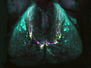

Crossed Bones

Understanding bone tumours by watching them as they grow

Cancers that spread to bones are often difficult to treat, but finding out how tumour and bone cells live side by side may help to heal osteolytic lesions – tears created in bone tissue as a tumour grows inside. Intravital microscopy watches as this lesion, in mouse bone, widens over several days. From blue to green to red – consecutive overlapping pictures show the fringe of the hole eaten away by bone resorption – when bone cells are broken down. This bone tissue was actually grown in a lab under a mouse’s skin, with a thin surface ideal for peering through. Treating the lesion with a chemical called zoledronic acid slows the bone’s deterioration – just as it does in human patients – but doesn’t stop the cancer growing. Using biological models like this, scientists can now test combinations of drugs that preserve the bone, while targeting the cancer cells inside.